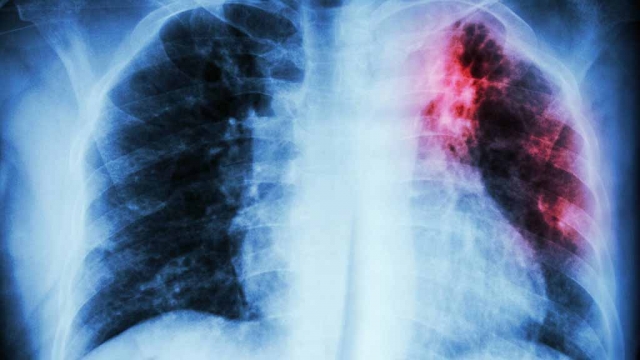

"Se trata de una patología que inflama y envejece los pulmones, dificultando el ingreso del oxígeno al organismo. La persona que la padece comienza a tener problemas para respirar, se fatiga con facilidad porque la sangre no se oxigena correctamente", enfatizó.

Los síntomas de la fibrosis pulmonar suelen confundirse con asma o "gripes mal curadas". Sin embargo, es crucial ir al médico si hay tos seca y persistente, sensación de ahogo, pérdida de peso, fatiga, dolor muscular, entre otros.